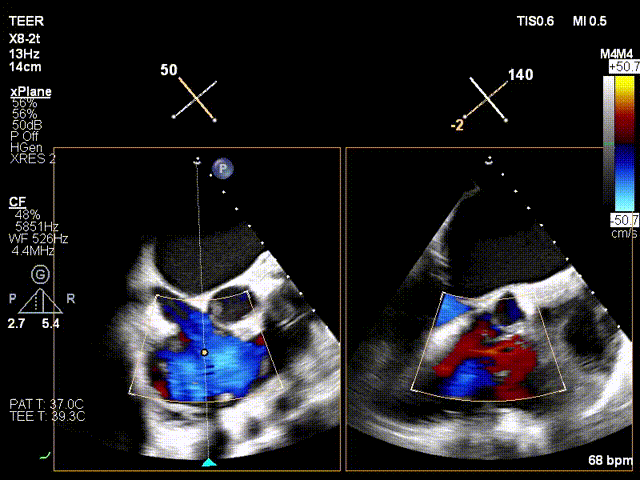

Regurgitation Outcome:

Critical regurgitation (5+) reduced to moderate to severe regurgitation (3+).

Postoperative moderate to severe regurgitation (3+)